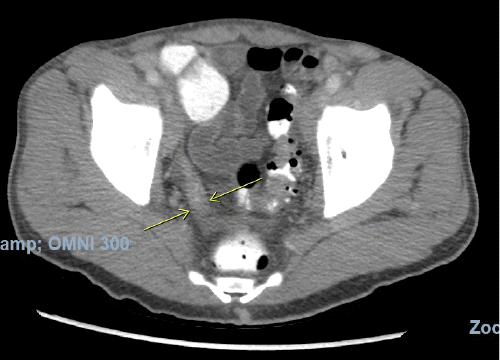

On physical examination, his vitals were within normal limits. He was very thin and had diffuse palpable lymphadenopathy in the cervical and inguinal regions and a large mobile left cheek mass. His abdominal exam was benign, with no anterior abdominal pain but rather bilateral flank pain. The patient's leukocytosis was 13,000 k/cm2, with the remainder of his labs within normal limits; the cluster of differentiation 4 (CD4) count was 2670, and the viral load was 1,391,823. HTLV-I/HTLV-II antibodies were positive. A CT of the abdomen and pelvis with oral and intravenous (IV) contrast was obtained, showing acute tip appendicitis (Figure 1) and extensive bulky gastrohepatic, periportal, peripancreatic, retroperitoneal/para-aortic, bilateral iliac chain, and bilateral inguinal lymphadenopathy (LAD) (Figure 2) with mild splenomegaly suggestive of lymphoma. A CT maxillofacial scan to evaluate his cheek mass also demonstrated extensive bulky cervical lymphadenopathy as well as an enlarged mandibular mass (Figure 3). Of note, the patient had a CT scan performed one year prior that showed an appendix with the same diameter but no local inflammation (Figure 4).

Figure 2. CT Scan: Abdominal and Inguinal Lymphadenopathy. Published with Permission